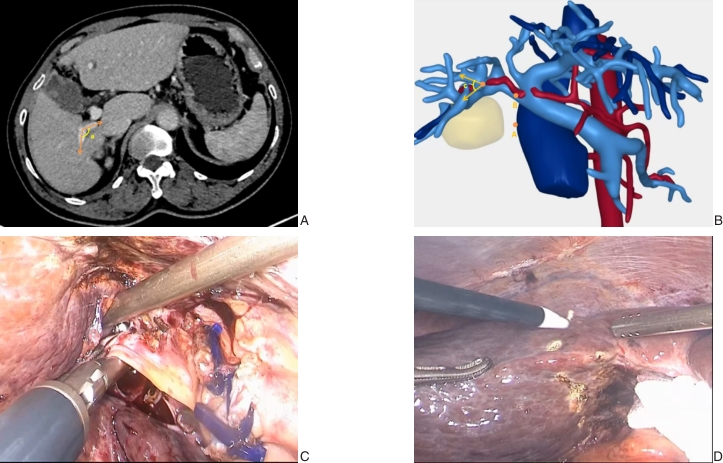

图5 应用本标志体系病例相关资料 A:CT图像标识a角;B:肝三维重建标识c角及肿瘤;C:沿Laennec膜分离Ⅵ段肝蒂;D:沿缺血线标记拟切除线Fig.5 Representative case illustrating the application of the anatomical landmark system A: CT image showing angle a; B: Three-dimensional liver reconstruction showing angle c and the tumor; C: Isolation of the segment Ⅵ Glissonian pedicle along the Laennecs membrane; D: Demarcation of the planned resection line along the ischemic line